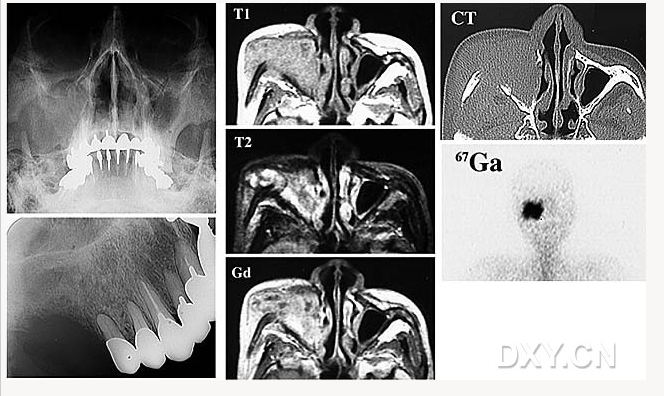

舍格倫綜合征